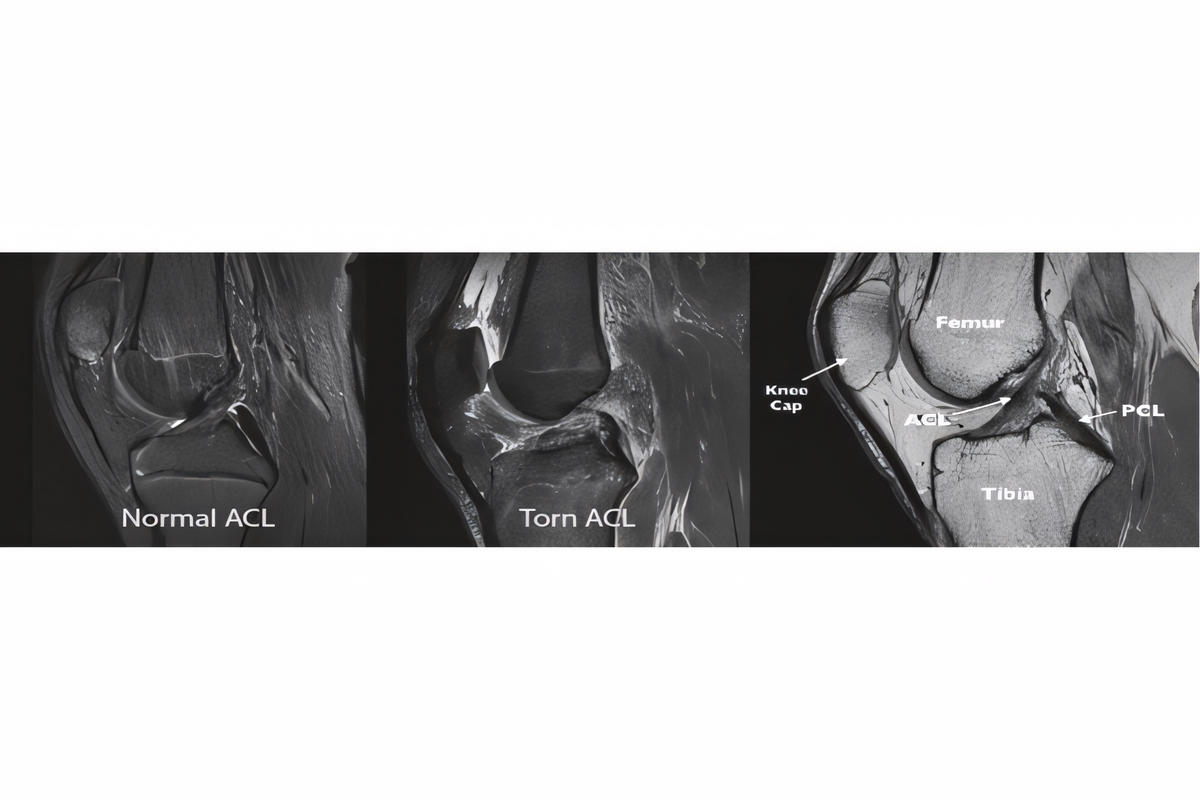

Απεικονιστικός έλεγχος

Ακτινογραφίες για αποκλεισμό οστικών κακώσεων

Μαγνητική τομογραφία (MRI), που επιβεβαιώνει τη ρήξη πρόσθιου χιαστού και αναδεικνύει συνοδές βλάβες σε μηνίσκους, χόνδρο ή πλάγιους συνδέσμους

Η MRI αποτελεί την εξέταση εκλογής για την τεκμηρίωση της βλάβης.